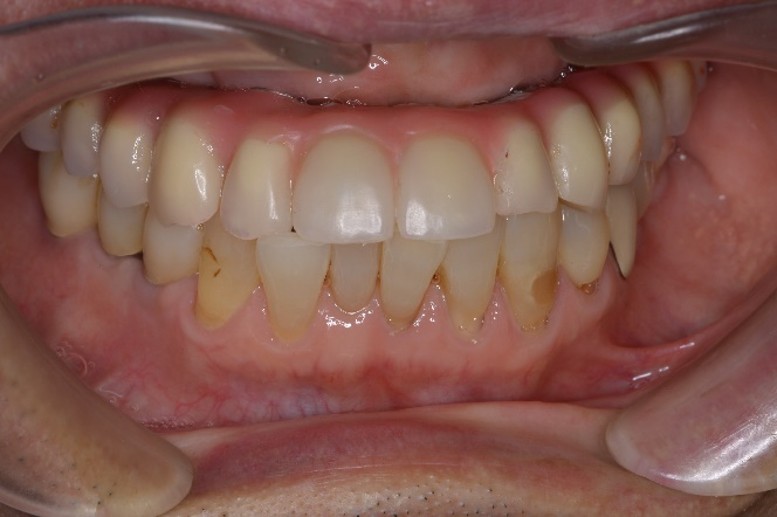

当院にて、歯周病治療で口腔内環境を整えた上でインプラント治療を行った結果、ご自身の歯のような見た目と噛み心地を回復。「人前で笑えるようになった」「食事が美味しい」と、健康な人と全く変わらない人生を取り戻されました。

治療後(口腔内写真)